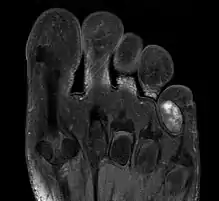

| Chondroma of the soft parts located in the little toe. | |

Extraskeletal chondroma is a cutaneous condition, a rare benign tumor of mature cartilage.[1]